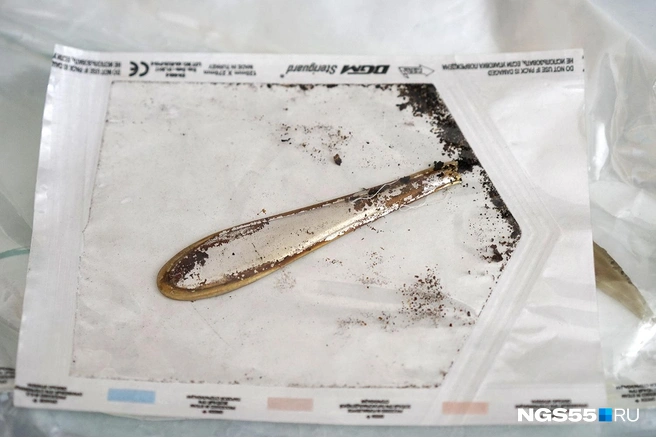

Такая история — и подобных у врачей отделения торакальной хирургии целая коробка. Свои находки они называют музеем инородных тел. Собрание, правда, неполное: часть изымают полиция и следком.

Врачи извлекают из лёгких много интересного. Из более-менее предсказуемого — ножи, пульки от воздушек и картечь от дробовиков, арматура... Всё это никогда не извлекают из пострадавших на месте, а бинтуют поверху и в таком виде доставляют хирургам.

Большую часть предметов, ставших орудиями человеческой жестокости, забирают силовики, но многое остаётся — людей с ножом в грудной клетке возят через день. Всякие есть — самодельные и заводские, металлические и керамические. Но все с застолий и с кровью.

Отдельная история — куриные кости, свечки от торта, чайные ложки... Попадался даже блистер от таблеток. Благополучно, как тот зуб, извлекаются не всегда — часто всё-таки приходится резать, если крупный предмет зашёл слишком далеко.

К жестоким, нелепым и трагичным историям хирурги привычны — хотя пациенты время от времени всё равно умудряются их удивлять. Потому врачи и держат в ординаторской свою коробку.